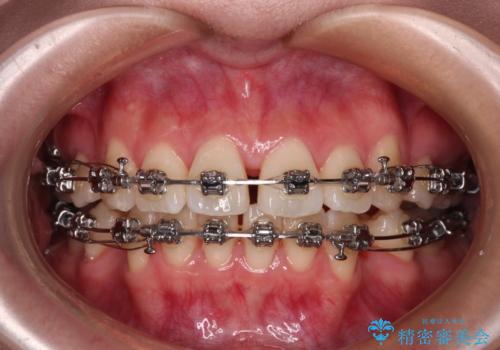

- 矯正装置

- メタルブラケット

- 前歯がくちばしのように飛び出していることを気にして来院された患者様です。

唇が前方に突出している横顔が気になっているため、上下左右の第一小臼歯4本を抜歯し、ワイヤー装置にて矯正治療を行うこととしました。

わずか2年弱で一気に口元が変化し、患者様には大変満足していただけました。